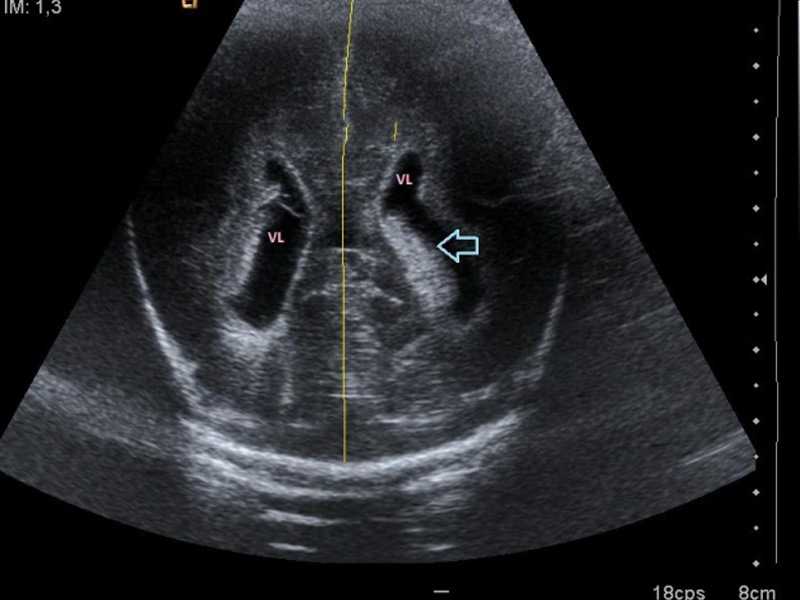

Cerebral

En los bebés, esta prueba se realiza con mayor frecuencia para evaluar las complicaciones del nacimiento prematuro. Un médico también puede solicitar una ecografía de cabeza para un bebé que presente signos de un aumento inusual en el tamaño de la cabeza, una fontanela abultada o algún síntoma neurológico.